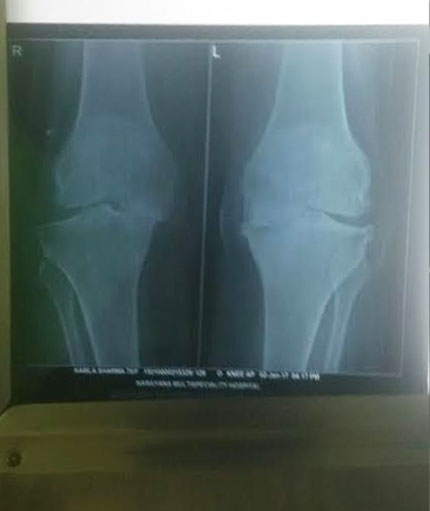

Knee Replacement

Knee replacement surgery otherwise knee arthroplasty, is a surgery involving the replacement of the damaged, diseased or distorted joint surfaces of the knee, with a prosthesis. As per the condition of the patient’s knees, the surgery can be performed as a partial knee replacement surgery or the total knee replacement surgery.